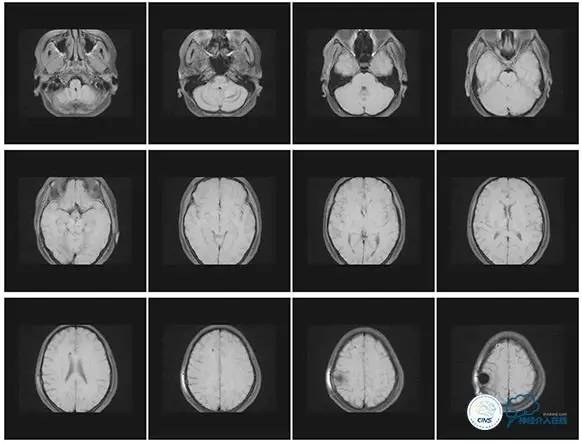

2016-5-19 MRI

2016-05-20 MRV

2016-06-03 CT

2017-06-07 CT